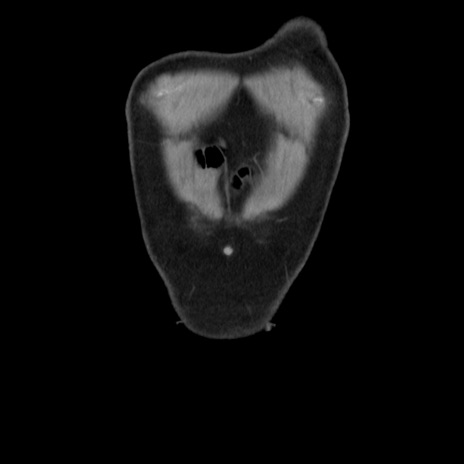

横断像